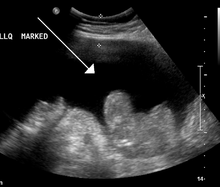

Ultrasound investigation is often performed prior to attempts to remove fluid from the abdomen. This may reveal the size and shape of the abdominal organs, and Doppler studies may show the direction of flow in the portal vein, as well as detecting Budd-Chiari syndrome (thrombosis of the hepatic vein) and portal vein thrombosis. Additionally, the sonographer can make an estimation of the amount of ascitic fluid, and difficult-to-drain ascites may be drained under ultrasound guidance. An abdominal CT scan is a more accurate alternate to reveal abdominal organ structure and morphology.

- Grade 1: mild, only visible on ultrasound and CT